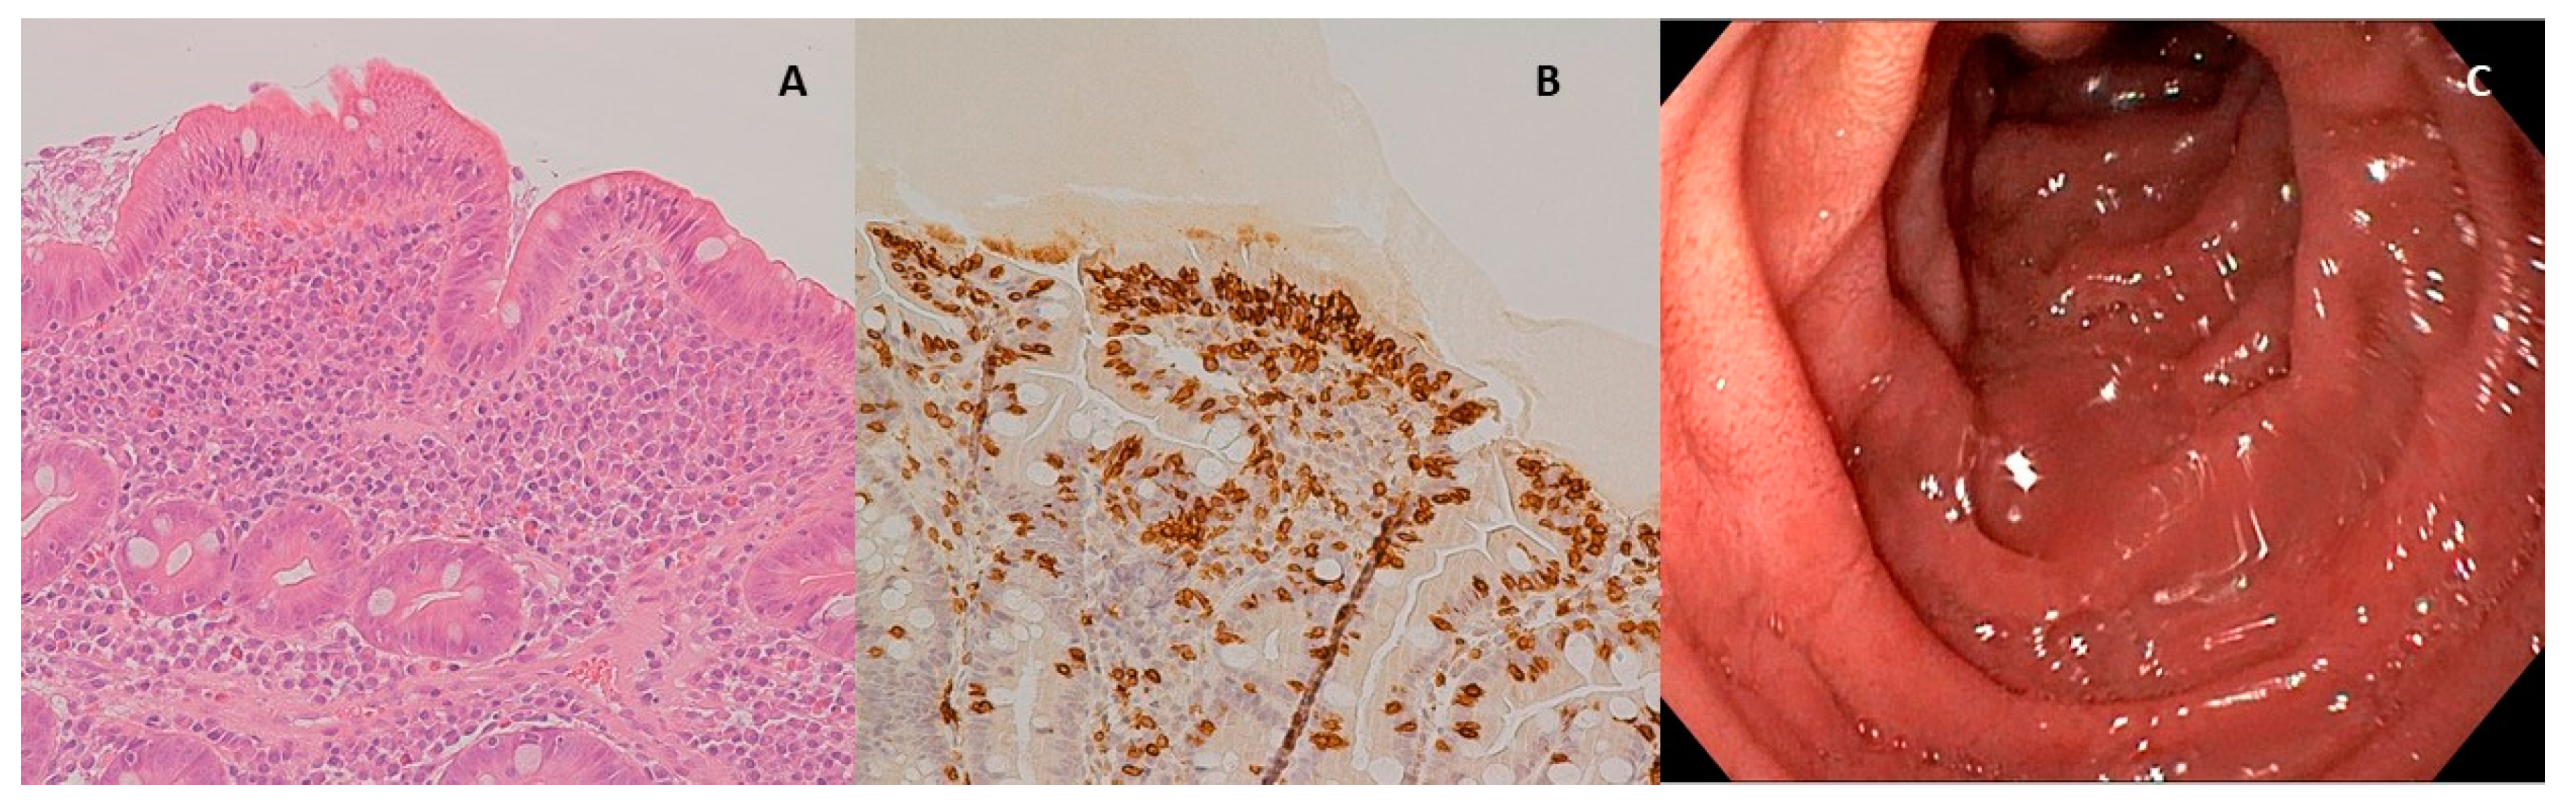

- Oberhuber, G. Histopathology of celiac disease. Biomed. Pharmacother. 2000, 54, 368–372. [Google Scholar] [CrossRef]